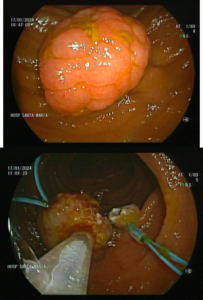

Síndrome de Peutz-Jeghers

Hospital Santa Maria (Lisboa)